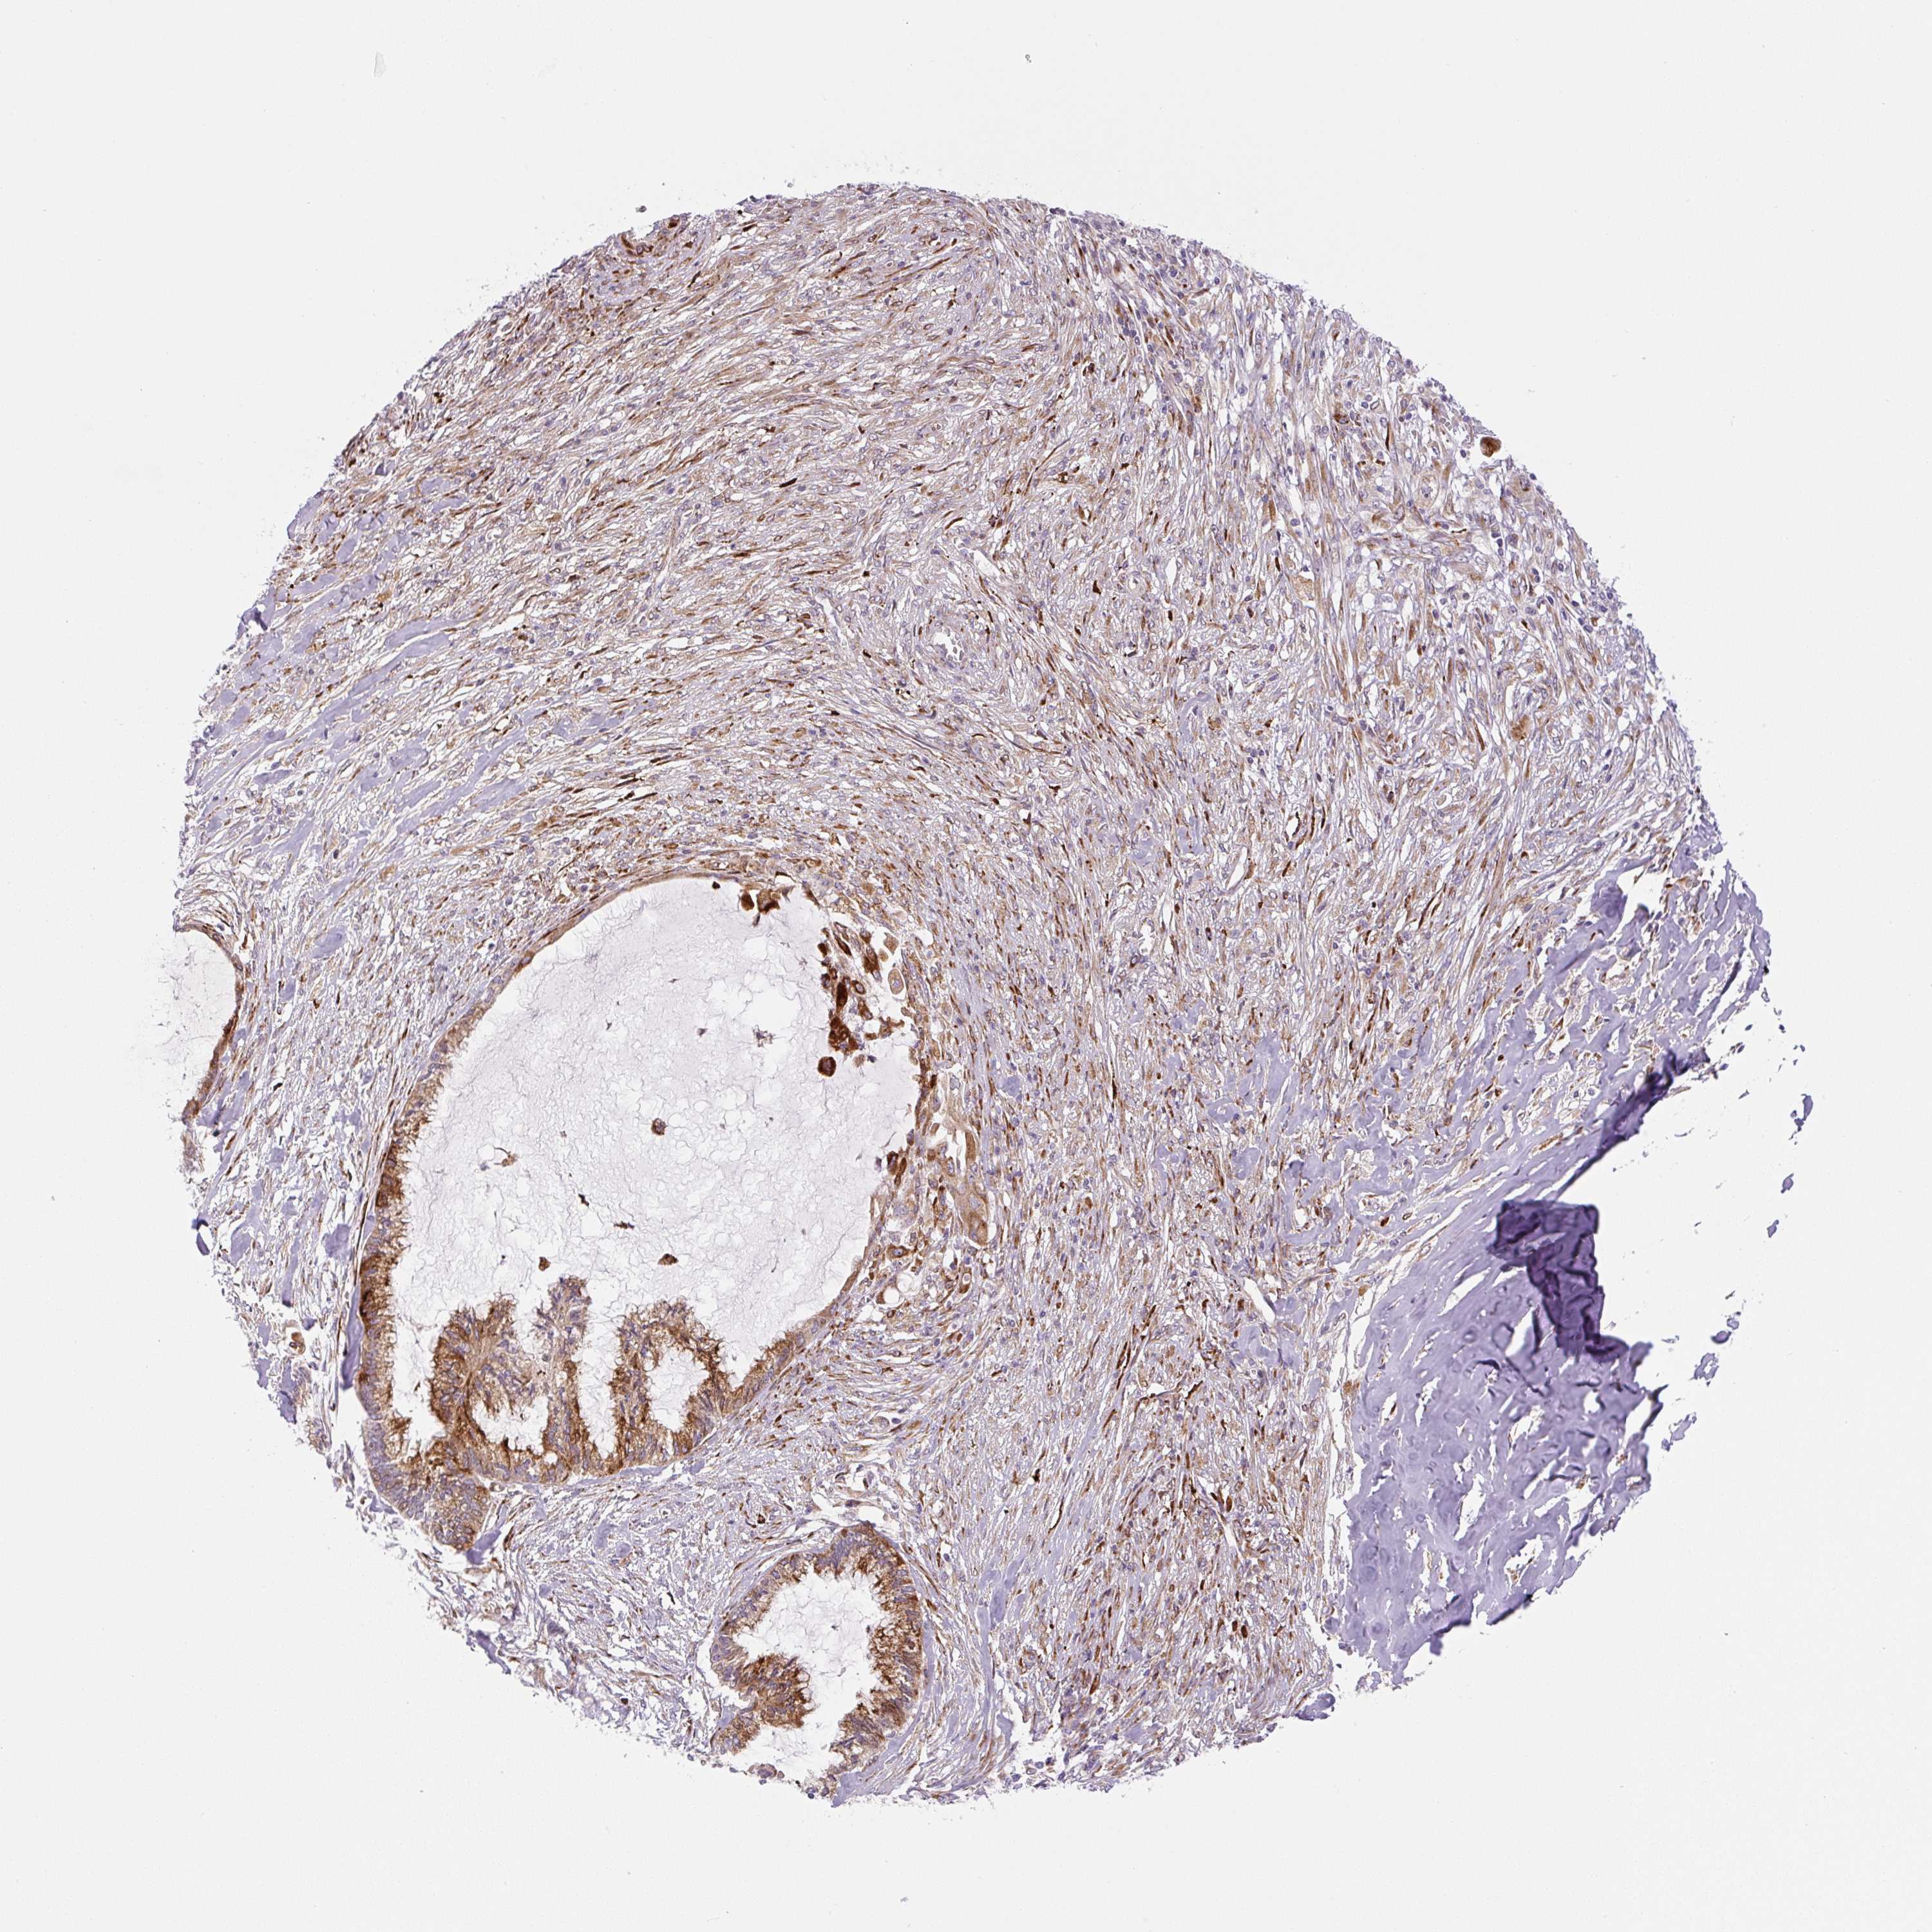

ENDOMETRIAL CANCER - Protein expressioni

A mouse-over function shows sample information and annotation data. Click on an image to view it in a full screen mode. Samples can be filtered based on level of antibody staining by selecting one or several of the following categories: high, medium, low and not detected. The assay and annotation is described here.

Note that samples used for immunohistochemistry by the Human Protein Atlas do not correspond to samples in the TCGA dataset.

Antibody stainingi

Antibody staining in the annotated cell types in the current human tissue is reported as not detected, low, medium, or high, based on conventional immunohistochemistry profiling in selected tissues. This score is based on the combination of the staining intensity and fraction of stained cells.

Each image is clickable and will lead to virtual microscopy that enables deeper exploration of all samples and also displays staining intensity scores, fraction scores and subcellular localization as well as patient and tissue information for each sample.

Antibody HPA054579

Staining

High

Medium

Low

Not detected

Intensity

Strong

Moderate

Weak

Negative

Quantity

>75%

75%-25%

<25%

None

Location

Nuclear

Cytoplasmic/membranous

Cytoplasmic/membranous,nuclear

Adenocarcinoma, NOS

Adenocarcinoma, metastatic, NOS